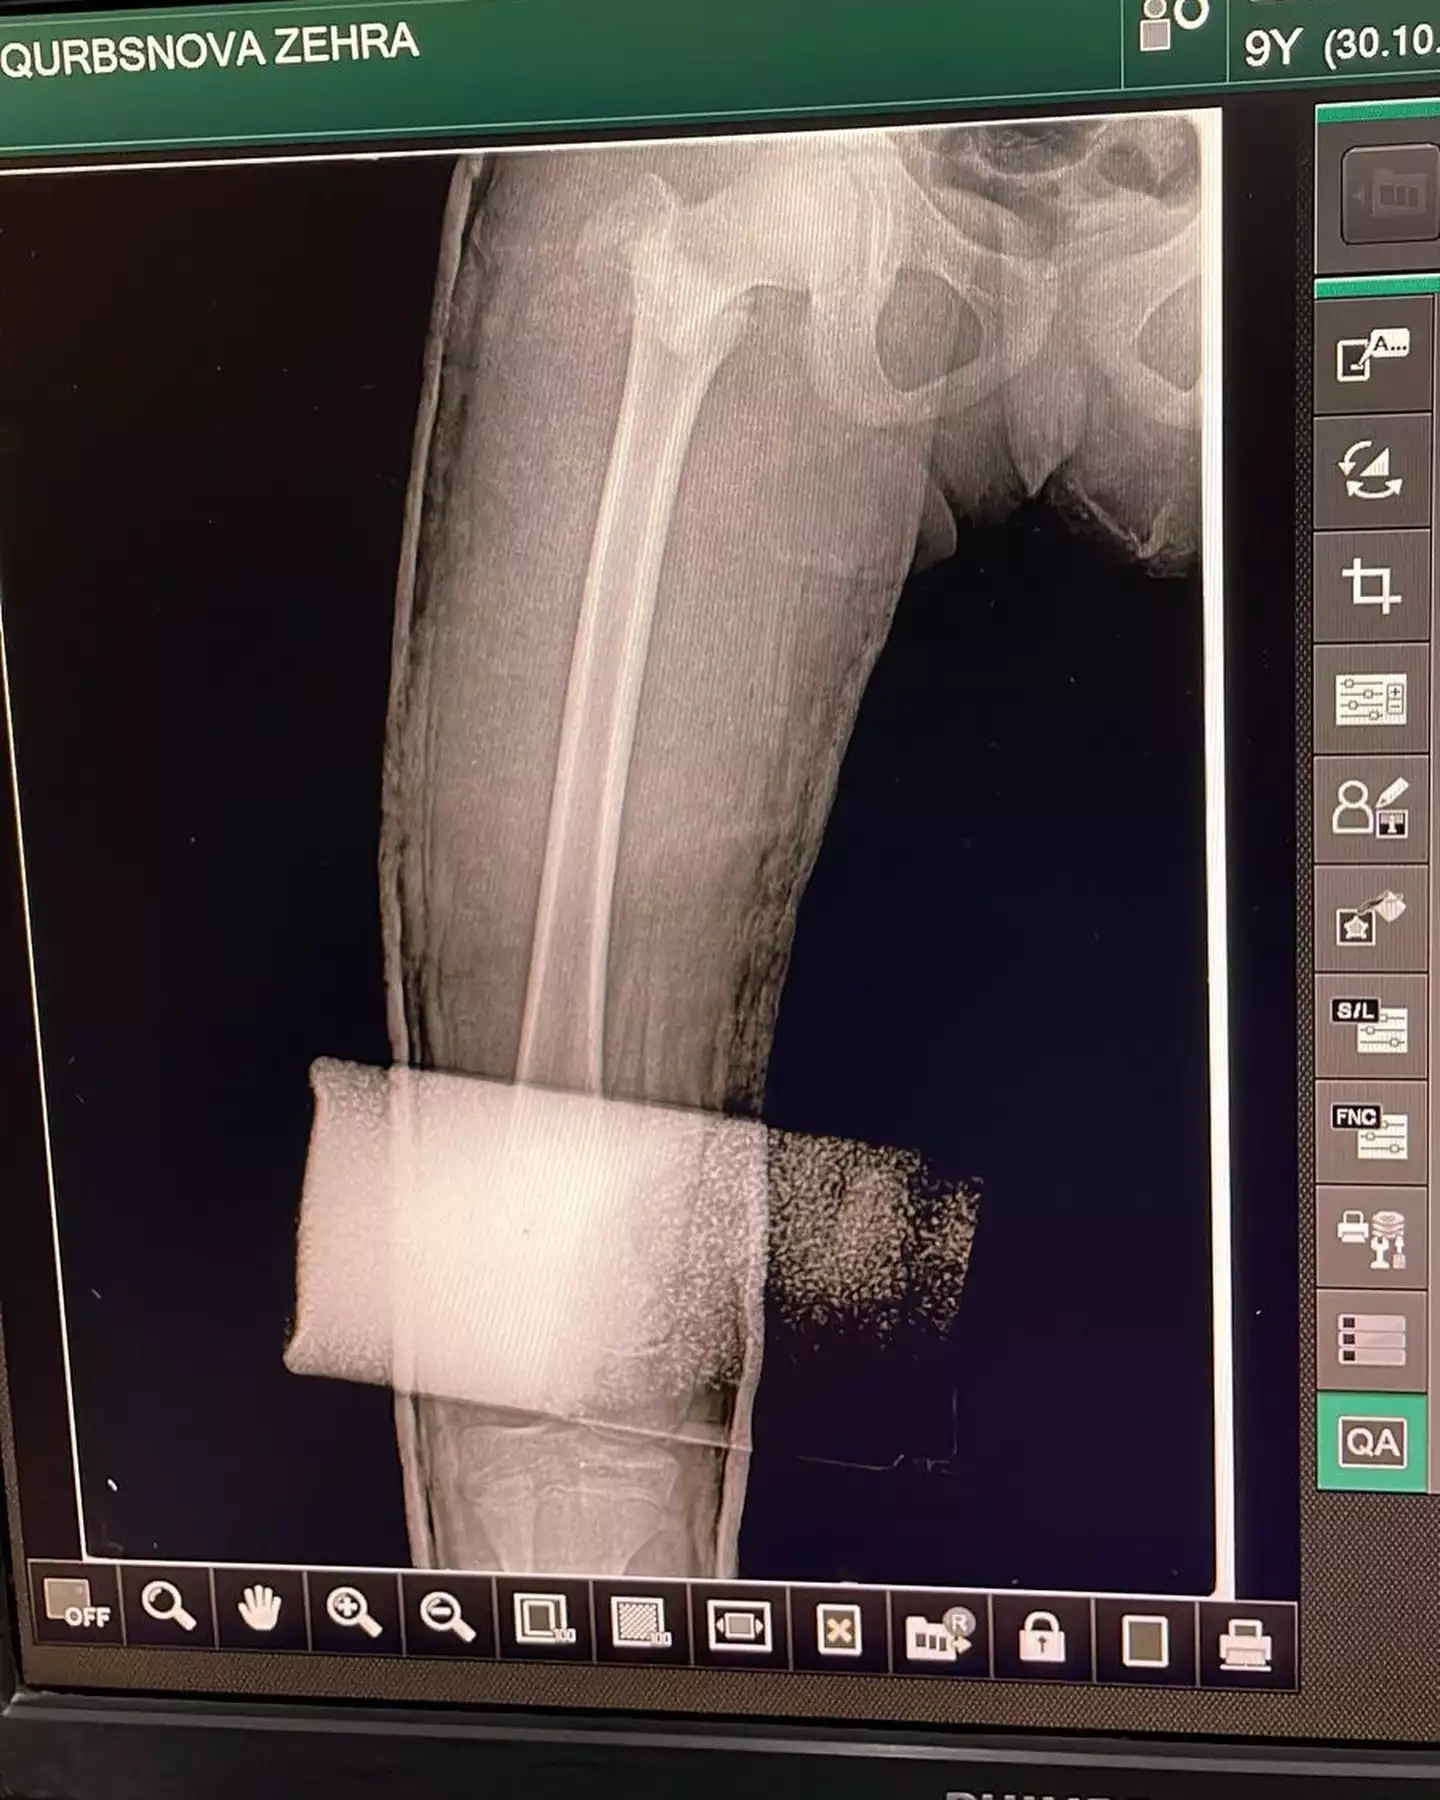

Hadisədən yalnız iki azyaşlı xilas ola bilib. Nərmin bildirib ki, onların da səhhətlərində ciddi problemlər yaranıb və maddi dəstəyə ehtiyacları var.